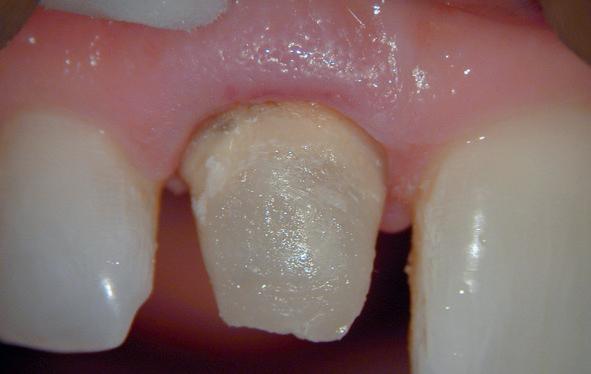

Een 47-jarige collega presenteert zich in onze verwijspraktijk voor endodontie. Hij heeft enige tijd geleden zijn kroon op de 11 laten vervangen (afbeelding 1). Omdat er geen klinische en röntgenologische aanwijzingen waren voor een periapicale laesie of een insufficiënte wortelkanaalbehandeling van de 11, werd besloten de endo, die dateerde van meer dan 30 jaar geleden, niet te reviseren (afbeelding 2). Tijdens een routinematige gebitsreiniging constateert zijn mondhygiënist een pocket van 7 mm aan de mesiopalatinale zijde van 11 (afbeelding 3). De nieuwe kroon wordt tijdelijk gecementeerd, en omdat

1: Klinische foto van bovenfront

3: Pocket palatinaal 11